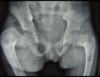

Espondilite anquilosante

Homens jovens, 3 década

Sacroileíte bilateral e simétrica

Coluna: Shiny corners (romanus): erosões nos cantos vertebrais com esclerose reativa;

vértebra quadrada (perda da concavidade anterior); espondilodiscite não infecciosa (lesão de andersson); aparência em bambu (anquilose dos sindesmófitos); sinal da faca (ossificação central - ligamento interespinhoso no rx ap),